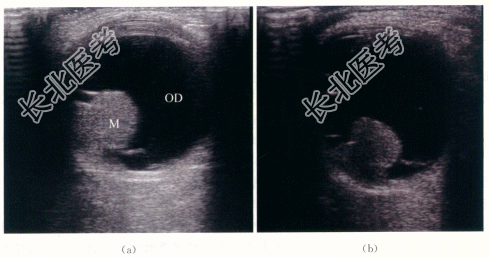

- [材料题] 患者,男性,52岁,因“右眼视力逐渐下降半年.眼前黑影伴视物变形1周”就诊。体格检查:患者视野检查示蓝色视野缺损大于红色视野缺损。特殊检查:眼底检查示右眼玻璃体混浊。颞侧可见脉络膜实性隆起,呈棕褐色,表面有出血。隆起物周边视网膜呈青灰色隆起。影像资料如下:

- 简答题1、该患者的超声诊断是什么?